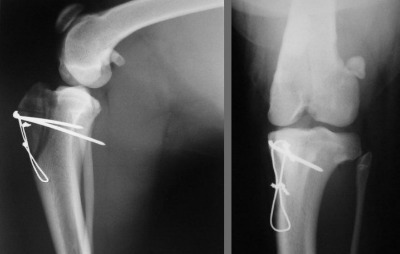

Kontrollbilder

Scheibe ist plaziert, fixiert und verdrahtet, dieses Implantat wird nun in dem Knie bleiben. Alles wird nun sauber vernäht.